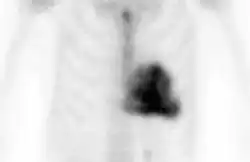

DPD scan

A DPD scan is a type of nuclear medicine imaging test which uses radioactive technetium-99m (99mTc) and 3,3-diphosphono-1,2-propanodicarboxylic acid (DPD) to diagnose cardiac amyloidosis. The radiopharmaceutical is taken up only in patients with ATTR amyloidosis, making it a useful tool to differentiate from AL amyloidosis.[1]